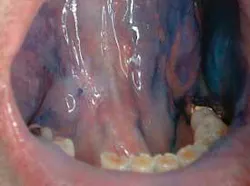

The clinical examples below show the appearance of lesions under incandescent light, chemiluminescence, and finally, the TBlue630â„¢ stain.

Malignancies often begin with preneoplastic lesions, such as leukoplakia (white lesions). Twenty percent of leukoplakias display cellular dysplasia.This entity represents 85 percent of oral premalignant lesions. Erythroplakia (red lesions) and erythroleukoplakia (combination of white and red lesions), generally seen in elderly males, are severely dysplastic or have undergone malignant changes 91 percent of the time. These changes may be very difficult to see in their early stages depending on where they are located in the oral cavity.21-24

The light source is a disposable light stick contained within a retractor. The patient rinses with a flavored acetic acid solution, and then is examined. Normal epithelium absorbs the light and appears darker than abnormal epithelium, which reflects the light. As cells become dysplastic, the nuclear/cytoplasmic ratio increases. The enlarged nuclei reflect the chemiluminescent light, even from below the basement membrane. The lesion is marked on a mouth map provided in the kit, and photographed if possible. If inflammation or trauma cannot be ruled out, the patient returns in seven to 14 days. If the lesion persists, the toluidine blue (TBlue630™) dye is swabbed onto the site. Retention of the TBlue630™ indicates a need for referral for further study or biopsy. The TBlue630™ follow-up has a very high sensitivity and negative predictive value. There are very few false positives associated with this protocol. One study showed that TBlue630™ detected 16 out of 17 high-grade dysplasias.35 Other studies have indicated the extreme sensitivity of toluidine blue staining of premalignant lesions, including identification of lesions with negative biopsies that eventually converted to malignancies.36-38 The entire screening with the ViziLite® Plus kit takes less than three minutes and can be performed by a hygienist.